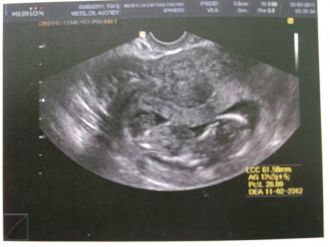

3e échographie

Le 02 aout 2011 :

Enceinte de 11 SG+1, enfin l'écho du 1er trimestre!!

Tous vas très bien, il mesure 61.58mm, son petit cœur bat très bien!!! Sa clarté nucale est excellente!!! Sa petite tête fais 22.42 mm!!!

Enfin nous allons pouvoir le crier sur tous le toit!!! Tous vas bien pas d'anomalie!!!!

Message déposé le 16.08.2011 à 09:49 - Commentaires (1)